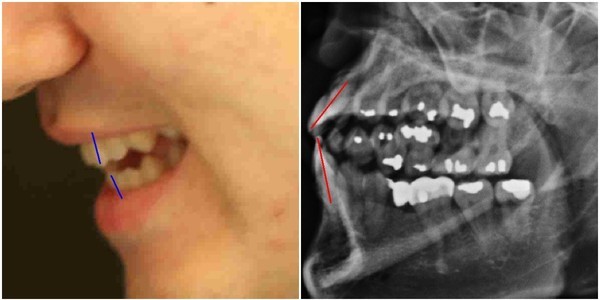

- ▲ 박주신씨 명의의 자생병원 엑스레이와 주신씨의 실물사진 비교. ⓒ 뉴데일리DB

‘박주신씨 병역비리 의혹’을 제기하다가 공직선거법 위반(낙선목적 허위사실 유포) 혐의로 재판을 받고 있는 ‘양승오 박사 재판’ 피고인들이, 주장의 근거로 들고 있는 주요 증거 가운데 하나가, 박주신씨 명의의 엑스레이 속 피사체의 치아상태를 볼 수 있는 구외 엑스레이(이하 치아 엑스레이)다.

양승오 박사 등에 대한 검찰의 수사가 진행되던 지난해, 이 사건 피고인들은 박주신씨 치아 X-Ray를 근거로, 박주신씨의 신체를 촬영했다는 X-Ray 속 피사체가 제3의 인물일 가능성을 주장했다.

문제의 액스레이는 박주신씨가 병역변경처분을 받기 위해 자생병원에서 MRI를 촬영하면서 함께 찍은 것으로 알려져 있다.

피고인들이 치아 X-Ray를 근거로, '피사체 바꿔치기' 의혹을 강하게 제기한 이유는, X-Ray에 나타난 치아의 상태가, 도저히 20대 중반 청년의 것이라고는 보기 힘든 특징을 갖고 있었기 때문이다.

주신씨 치아 X-Ray 사진을 보면, 치아 상태가 매우 불량하다는 사실을 알 수 있다. 치아 3개는 발치된 채 방치돼 있고, 아말감으로 때운 치아가 무려 14개에 달한다.

- ▲ ▲치과의사 문씨가 촬영한 것으로 알려진 박주신씨 명의의 치아 엑스레이 자료. ⓒ 차기환 변호사

- ▲ 박주신씨 치아 엑스레이 분석자료. ⓒ 뉴데일리DB

아말감(Amalgam) 치료는 변색 등 여러 가지 단점을 갖고 있어 사용빈도가 크게 줄고 있다는 것이 치과의료계의 공통된 평가다.

서울 방배동에 사는 중산층 청년이, 치과의사는 물론 환자들도 기피하는 아말감을 이용한 치과 치료를 이처럼 많이 받았다는 것은, 쉽게 받아들이기 어렵다는 것이 양승오 박사 재판 피고인들의 지적이다.

피고인들은 주신씨 명의의 치아 엑스레이를 보면, 하악 좌측 1소구치(아래쪽 좌측 첫 번째 작은 어금니)까지 아말감으로 치료한 사실을 확인할 수 있다며, 이런 경우는 매우 드물다고 지적하고 있다.

이 사건 피고인 중 한명인 치과의사 김우현씨는, 주신씨의 영구치가 맹출을 시작했을 것으로 추정되는 1990년대 중반 이후, 젊은 사람이 1소구치를 포함한 구치부 치아 전체를 아말감으로 치료했다고 보기엔 무리가 있다고 입장을 밝혔다.

치의학 박사 C씨는 뉴데일리와 기자와의 인터뷰에서 “주신씨의 전체적인 치료 상태를 보면, 소위 말하는 '야매'로 했을 가능성이 높다”는 의학적 소견을 내놓기도 했다.

“(주신씨의 것이라고 알려진 구외 X-Ray 사진을 보면) 최근 국내에서 교육받은 치과의사의 치료라고 생각할 수 없을 정도.”

“(주신씨 구외 X-Ray 사진 상의) 45번, 46번 보철치료 및 치아 상실 문제도 마찬가지다. 보철물로는 상당히 저렴한 비귀금속 합금을 사용한 것으로 보인다. 37번 치아는 아예 없는 상태로 방치돼 있다.”

“박주신씨의 가정환경을 고려하면, 이런 치료를 받았을 가능성은 1%도 안 된다. 서울 방배동에 거주했던 중산층 이상의 가정에서는 흔치 않은 상황.”